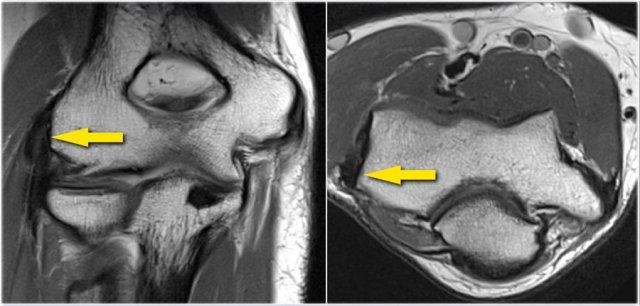

Pseudodefect of the capitellum

Đây là một phát hiện mà bạn thường thấy trên các hình ảnh mặt phẳng coronal.

Trông có vẻ giống như một tổn thương sụn xương, nhưng nếu bạn nhìn vào hình ảnh mặt phẳng sagittal, bạn sẽ nhận thấy rằng hình ảnh mặt phẳng coronal đi qua phần không có khớp phía sau của chỏm con.

Vì vậy, khi khuỷu tay duỗi hoàn toàn, một phần của chỏm quay thực sự nằm phía sau bề mặt sụn khớp của chỏm con.

Trên hình ảnh mặt phẳng coronal, chúng ta sẽ quan sát thấy chỏm quay được bao phủ bởi sụn và đối diện với nó là phần không được bao phủ bởi sụn của chỏm con, phần này thường có phần không đều.